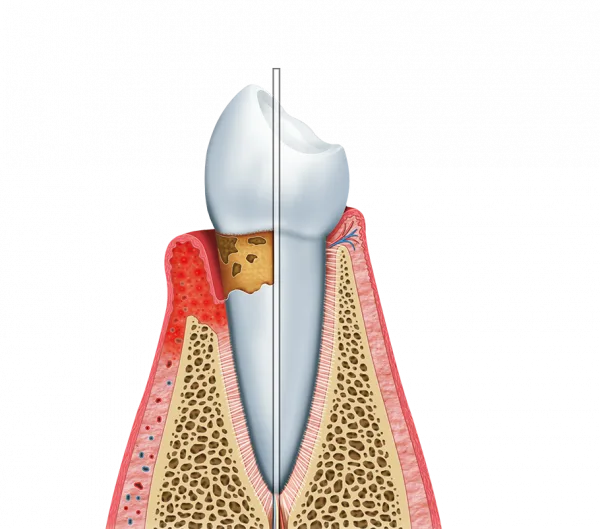

A análise clínica é fundamental para prevenir doenças periodontais. Essas condições, quando não tratadas, podem levar à perda de dentes e outras complicações severas.

Identificação precoce de quadros de gengivite;

Tratamento de periodontite antes que ocorra perda óssea;

Redução do risco de infecções bucais persistentes.

Verificação de bolsas periodontais e retrações;

Detecção de acúmulo de tártaro e placa bacteriana;

Avaliação da saúde do osso ao redor das raízes.

Durante a avaliação gengival dentista, o especialista realizará uma série de testes específicos. Isso inclui a verificação da cor, textura e volume das gengivas, além da análise da estabilidade dos dentes.

Exame visual criterioso das mucosas e dentes;

Teste de profundidade das bolsas periodontais;